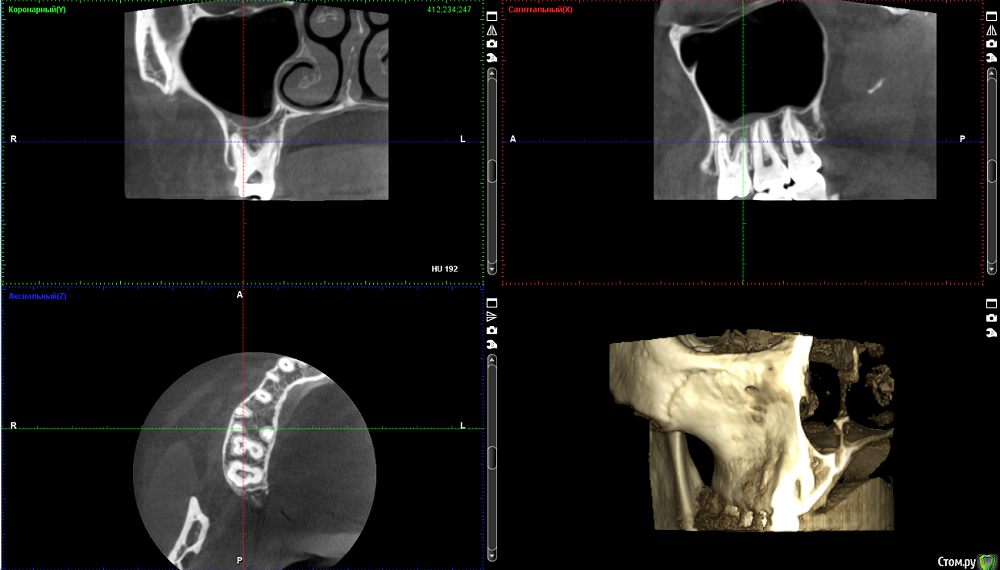

Стерхова Юлия Опубликовано 1 апреля, 2018 Автор Поделиться Опубликовано 1 апреля, 2018 Выкладываю старые срезы с опозданием(Я уже не знаю, как быть. Подскажите, пожалуйста! В общем, каналы уже месяц перелечиваются под микроскопом, диагноз - периодонтит. Примерно каждую неделю все прочищается и закладывается под временную пломбу лекарство, но результата нет - сохраняется боль в ночное время и во время очищения каналов. В гайморовой гранулёма. Несмотря на все это, хирург выступает категорически против удаления, терапевт тоже, на 7.04 запланирована пломбировка. Но на этой неделе я обратилась к ЛОРу, он поставил диагноз тонзиллит (на фоне инфицирования зуба), гайморит (из-за гранулёмы), а также нашел остаток пломбировочного материала в пазухе. Он - за удаление. Хирург наличие пломбы в пазухе отрицает. Кому верить в данной ситуации? Когда лучше сделать новое КТ: до или после пломбировки? И стоит ли пломбировать? Своим врачам я доверяю, но ЛОР заставил меня засомневаться, как и сохранение болей( Ссылка на комментарий

Стерхова Юлия Опубликовано 3 апреля, 2018 Автор Поделиться Опубликовано 3 апреля, 2018 Вот новые срезы КТ, сделанного вчера. Интересует белый кончик у канала (первый скриншот) - это резорбция? Ссылка на комментарий